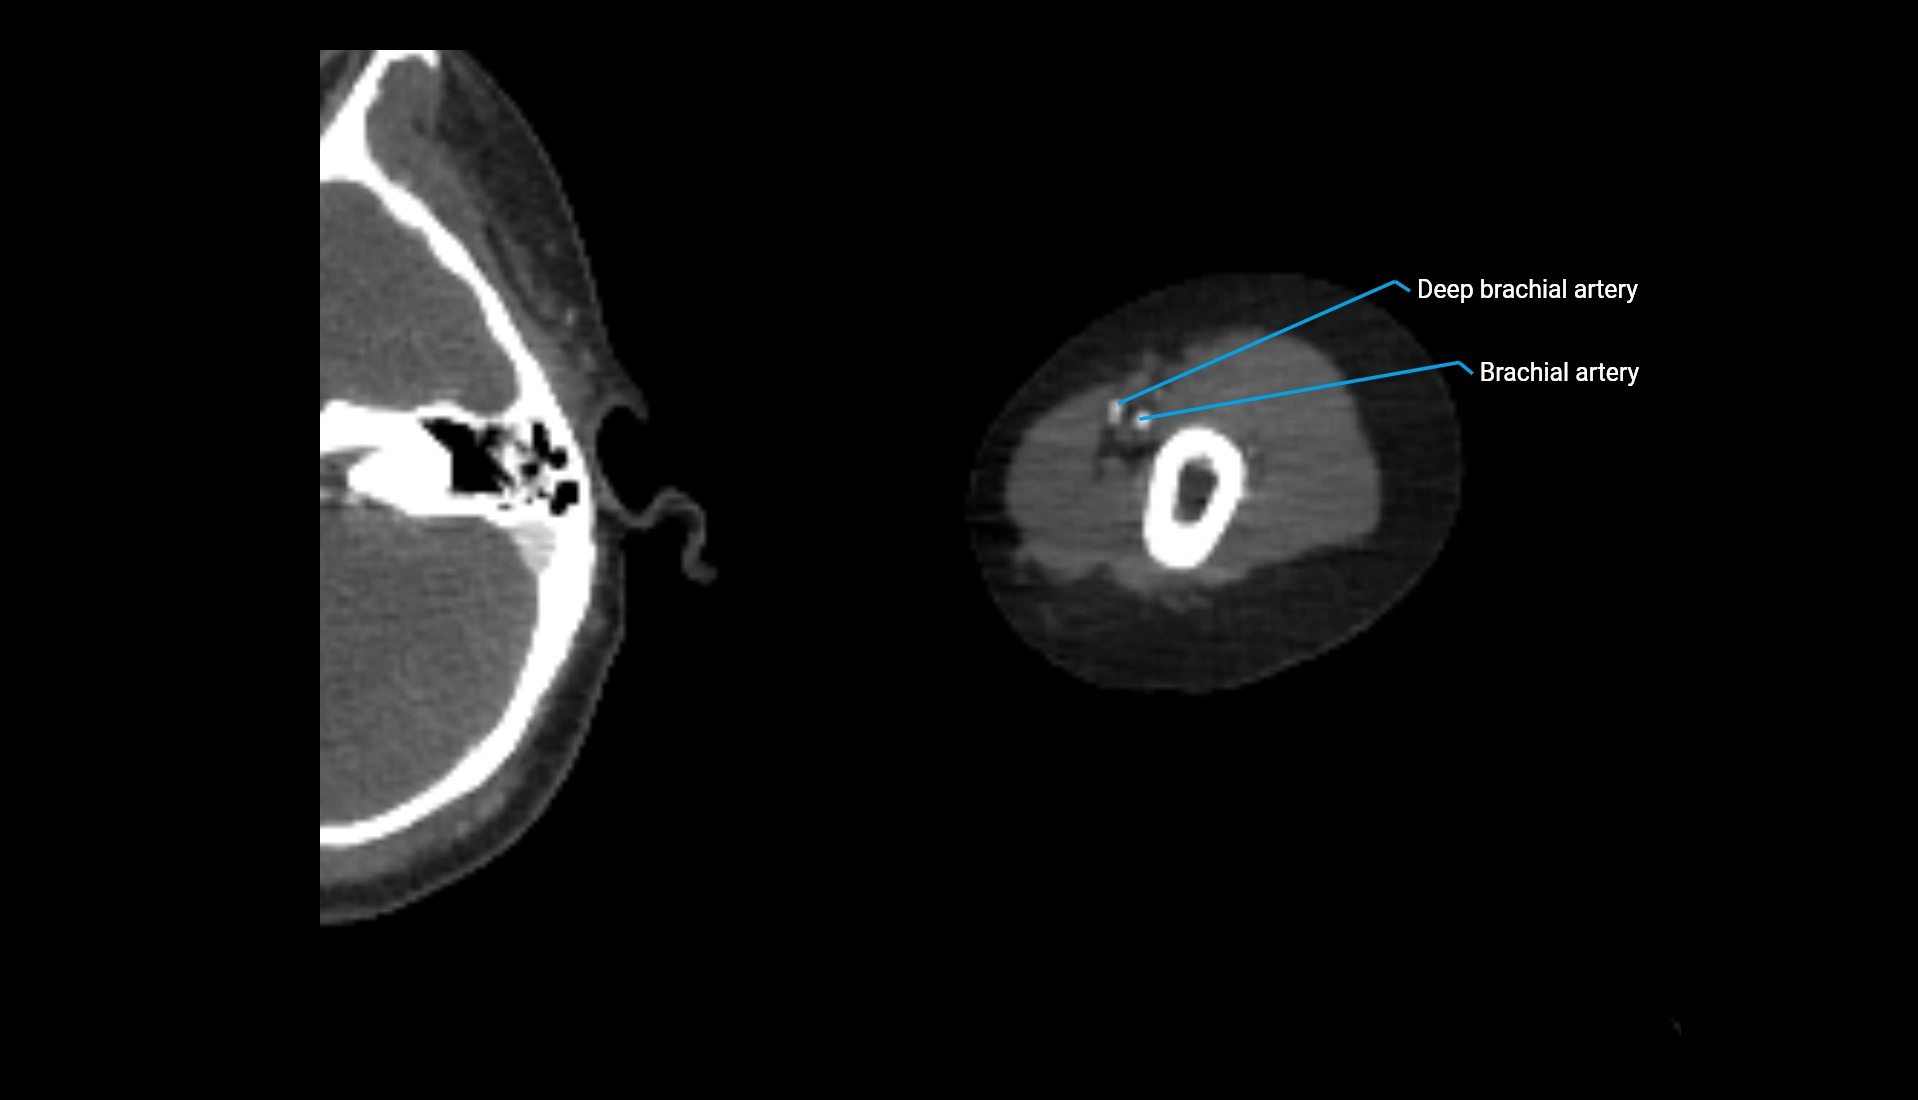

CT Appearance

Non-Contrast CT:

• Cortex: High-density, sharply defined

• Subchondral bone: Dense cancellous matrix

• Articular surface: Smooth concave contour articulating with the capitellum

• Excellent for evaluating bone integrity, alignment, and subtle fractures